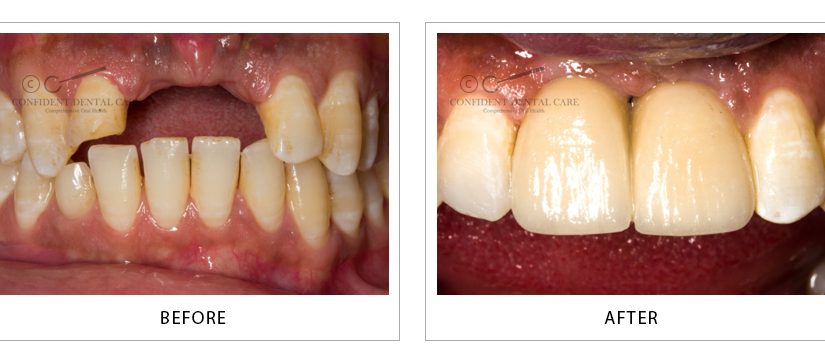

Implant Crown